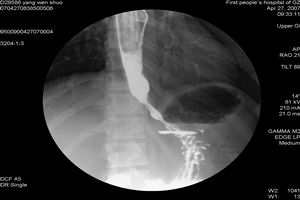

1.X線檢查胸部X線平片中有時可見擴張的食管,胃內氣泡消失。有肺炎或肺膿腫時肺野有改變。最常見的是胃氣泡消失。擴張明顯的食管在後前位胸片上像縱隔增寬,有時可見液平面,在側位片上見到氣管前移,早期病例,在X線檢查時可能不出現異常。2.鋇餐檢查食管鋇餐造影在失弛緩病例中是一項重要的診斷性檢查。檢查時要注意食管體部及遠端括約肌的形態學及功能特徵。X線電影照像或錄像較透視更能提供食管蠕動活動的動態觀察。檢查時病人取平臥位及站立位,以便觀察食管運動功能。若食管有明顯擴張或大量食物殘渣,造影前應插管吸出或沖洗,以免食物在X線影上與腫瘤混淆。失弛緩症的X線主要特徵為食管體部蠕動消失,吞咽時遠端括約肌失鬆弛反應,鋇在胃食管接合部停留。該部管壁光滑,管腔突然狹窄呈鳥嘴樣改變。